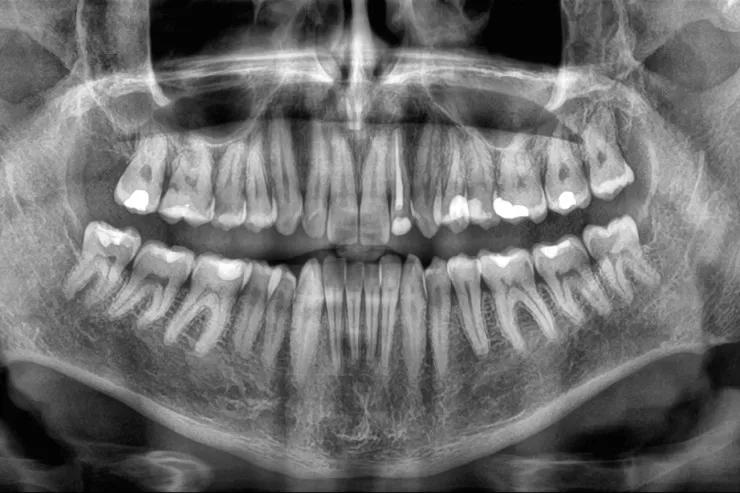

Yeni bir araşdırma göstərib ki, yaşlı insanlarda dişlərin sürətlə itirilməsi ölüm riskinin artması ilə əlaqəlidir. Çinli alimlər 3,5 il ərzində 8073 yaşlı insanı izləyərək belə nəticəyə gəliblər.

Moderator.az “sciencealert.com” portalına istinadla xəbər verir ki, tədqiqatın nəticələrinə görə, dişlərin itirilmə sürəti nə qədər yüksəkdirsə, bütün səbəblərdən ölüm riski də bir o qədər artır. Bu əlaqə yaş, cins, təhsil, içki və məşq vərdişləri kimi digər amillər nəzərə alındıqdan sonra da qalır. Mütəxəssislər bildirirlər ki, dişlərin itirilməsi birbaşa ölümə səbəb olmur, lakin diş itkisinə yol açan sağlamlıq problemləri, məsələn, iltihab, pis qidalanma və ürək xəstəlikləri ömrü qısalda bilər. Alimlər diş itkisinin insanın ümumi sağlamlıq vəziyyətini qiymətləndirmək üçün göstərici kimi istifadə oluna biləcəyini vurğulayırlar. Həkimlər dişlərin qorunması üçün müntəzəm diş həkimi müayinəsini, gündə iki dəfə fırçalamağı və siqaretdən uzaq durmağı tövsiyə edirlər.